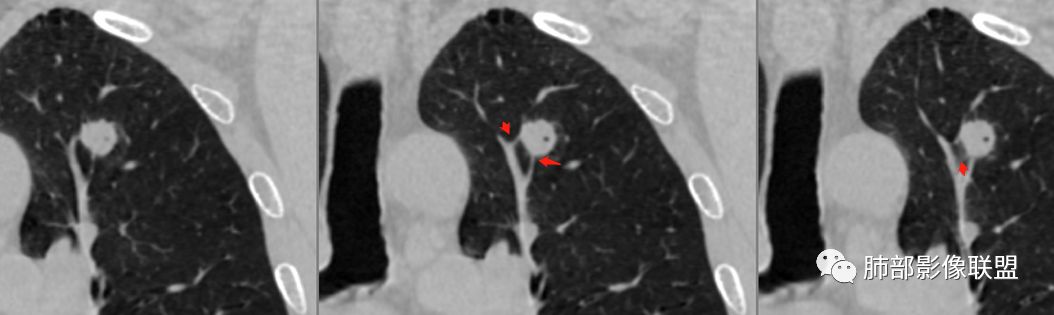

胸膜下结节,边界清楚、光滑,边缘稍凹陷,有胸膜牵拉

血管进入?

脐凹?

支气管在门口堵了

似有浅分叶

门口支气管堵塞——提示与支气管相关,不支持良性肿瘤

似乎有脐凹征

除了胸膜牵拉,还有短毛刺?血管纠集

支气管在门口堵塞

综合起来看,恶性不能排除。建议穿刺活检,一定要认清楚:我们影像有局限性。

病例1为胸膜下实性小结节,血管脐凹样出入,可见支气管阻塞。病灶膨隆,部分边缘平直,周围晕征不明显,未见分叶,但可见毛刺及胸膜牵拉,增强后明显强化,老年男性,怀疑新生物尤其是腺癌是有理由的。